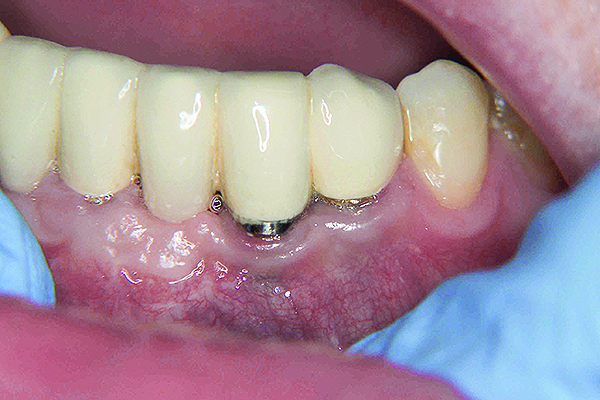

Fig 8. The implant on No. 23 4 years later with no maintenance care, showing increased inflammation and recession.

Figure 8